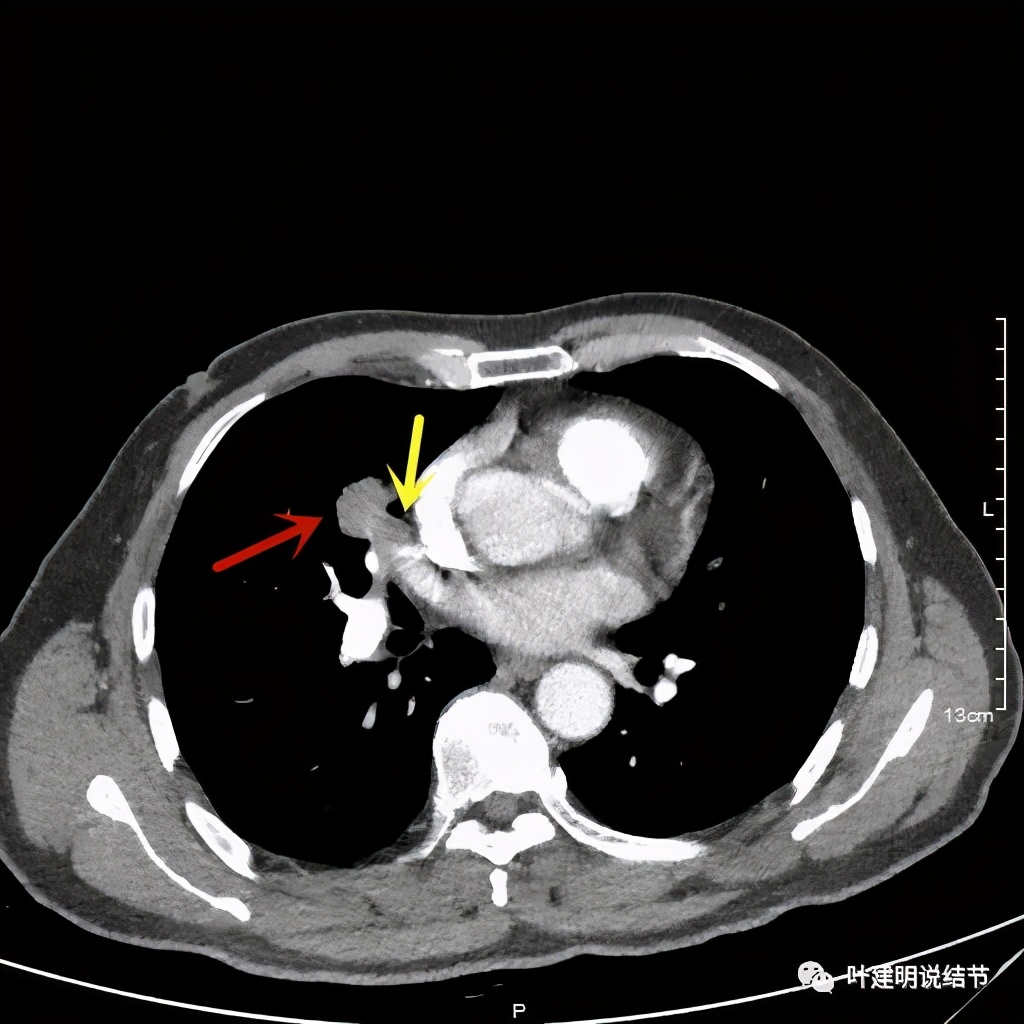

上图示血管被病灶影响,似乎有侵犯

上图示血管在病灶内挤压变细

上图示血管在病灶内被挤压